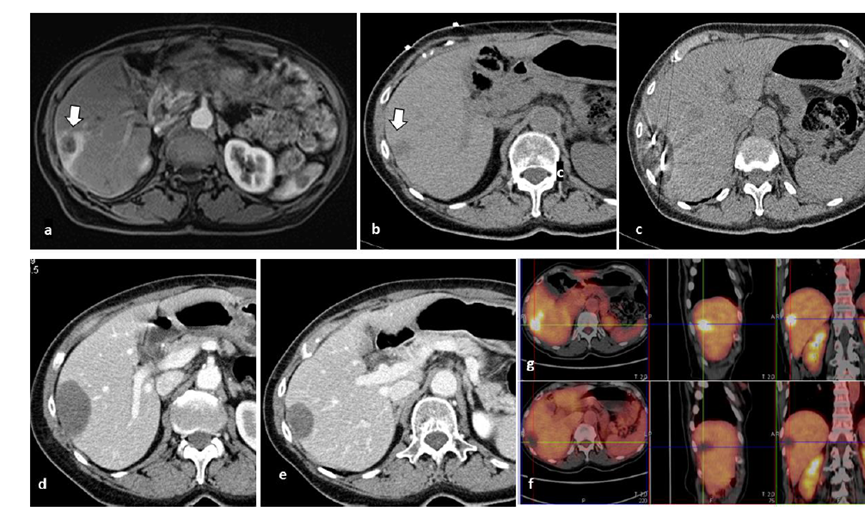

79 岁男性,肝转移(结直肠癌)肿瘤的完全消融病例

( a ) 轴向 MRI 和 ( b ) 轴向 CT 显示肝S8段有一个16mm的病灶,邻近肝缘。( c )冷冻消融期间CT显示放置了2个冷冻探针,低密度冰球包围病灶。(d)术后1个月随访 CT显示冰球对应的坏死区域,未见复发。(f)与基线影像(g)相比,12个月后的FDG-PET/CT显示未见FDG摄取。

技术成功100%,92% 的病灶中观察到肿瘤完全消融。16 名患者 (33%) 出现局部复发。10 名患者 (20%) 因局部复发或肿瘤消融不完全而接受二次冷冻消融术。